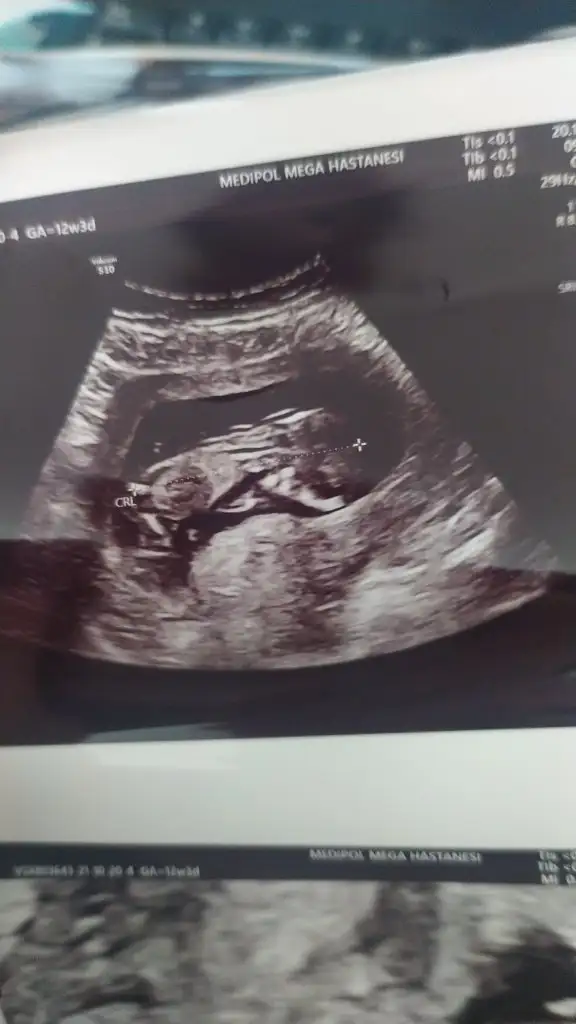

Benim ilk hamileliğim de 16. Haftama kadar doktor göstermedi deyip durmuştu ama ben erkek olduğunu 10. Haftamda anlamıştım kemik yapısından öyle de çıktı bildiğim şeyi doktor ancak 16. Haftada söyleyebildi

Kemik yapısından nasıl anlaşılıyor?

Eklentiler

• IMG_20200513_123238.webp

IMG_20200513_123238.webp

21,3 KB · Görüntüleme: 126